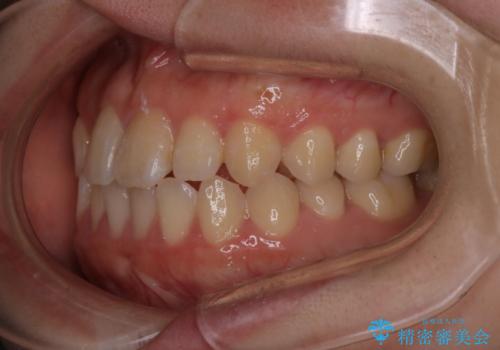

【インビザライン】前歯のがたつきを目立たない装置で治療

- 前歯の叢生を主訴に来院されました。目立たない装置を希望されたためインビザラインで治療を行いました。

IPRと拡大をし、叢生を治しました。右上2番は反対咬合でしたが短期間できれいに治りました。